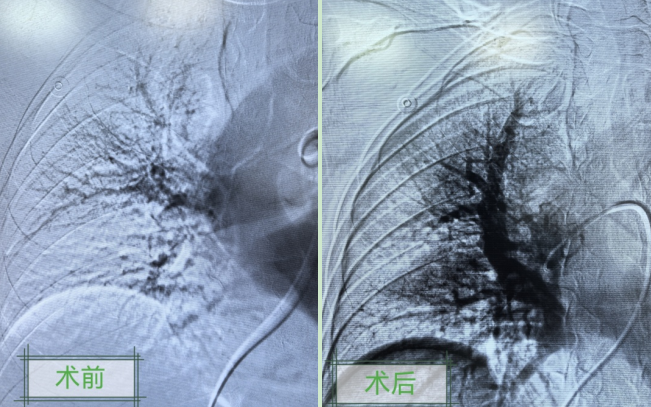

大年初三,凌晨1点钟,一名50多岁男子因“右下肢肿胀和呼吸困难”来到大竹县人民医院急诊科就诊,医生紧急完善肺动脉CT血管造影检查,提示为左右肺动脉多发充盈缺损,考虑肺动脉栓塞。介入科主任孙邱连夜为患者实施了介入手术,使其转危为安。当日,介入科还分别为四名急诊患者实施了DSA引导下颅内动脉瘤介入栓塞术、下肢深静脉血栓术和主动脉腔内隔绝手术。“正是因为急诊科准确识别了患者病情,并及时给予了紧急处理,才为我们介入团队赢得了宝贵的手术时间。”孙邱主任说。